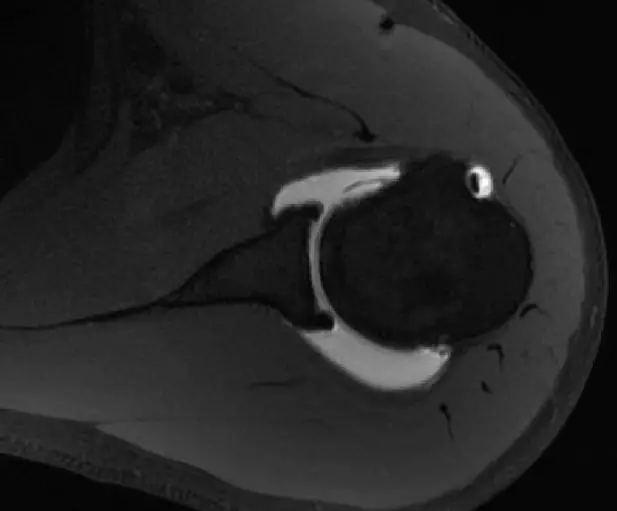

从这个层面可以看到前盂唇,后盂唇,质地均一的T2相低信号,它的前关节囊和后关节囊比较光滑,这是一个比较正常的前后盂唇的形态。